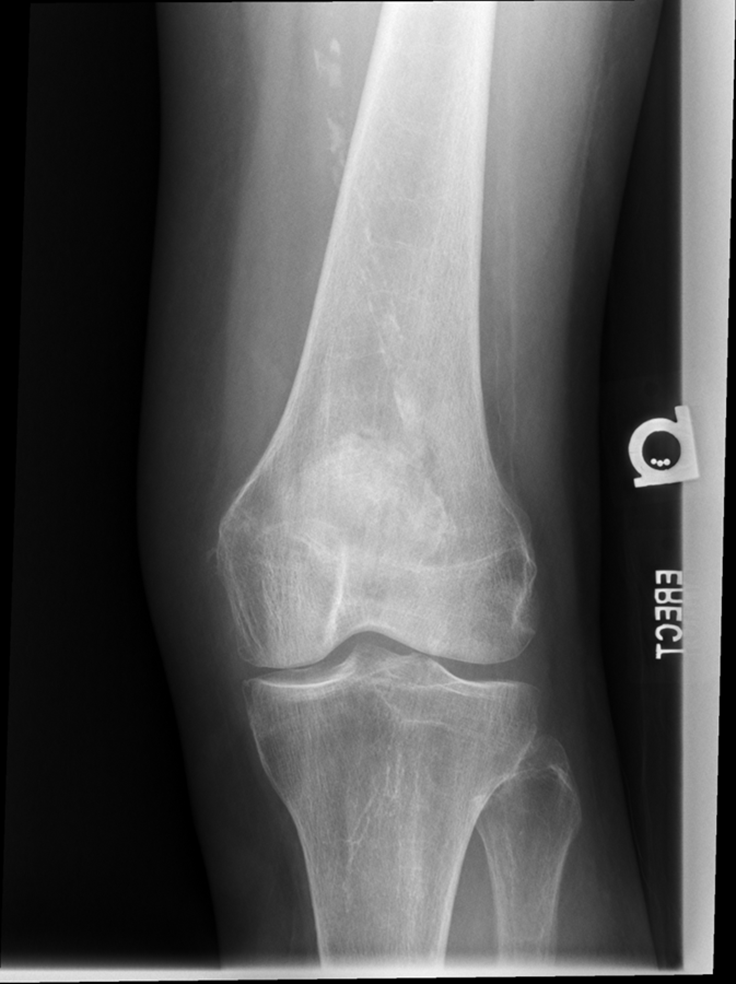

Trauma and Non Trauma AP Knee

•Evidence of proper collimation and the presence of a side marker placed clear of the anatomy of interest

•Knee fully extended if patient’s condition permits

•Entire knee without rotation

•Femoral condyles symmetric and tibia intercondylar eminence centered

•Slight superimposition of the fibular head if the tibia is normal

•Patella completely superimposed on the femur

•Open femorotibial joint space, with interspaces of equal width on both sides if the knee is normal

•Bony trabecular detail and surrounding soft tissues

Anatomy of the knee

Lateral Rotation, the fibular head is under the tibia, if patella is towards lateral side usually means it is laterally rotated.

Joint space is not open enough

The width of the joint space is not equal

REPEAT FOR LATERAL ROTATION

Not enough superimposition of the fibular head

Patella is in the center! good! equal distance of joint space/platoes which is good

ACCEPTABLE BECAUSE EVERYTHING ELSE IS GOOD! PATIENT COULD HAVE A MORE SEPARATED FIBULAR HEAD! THEIR ANATOMY IS DIFFERENT. CENTERING IS GOOD